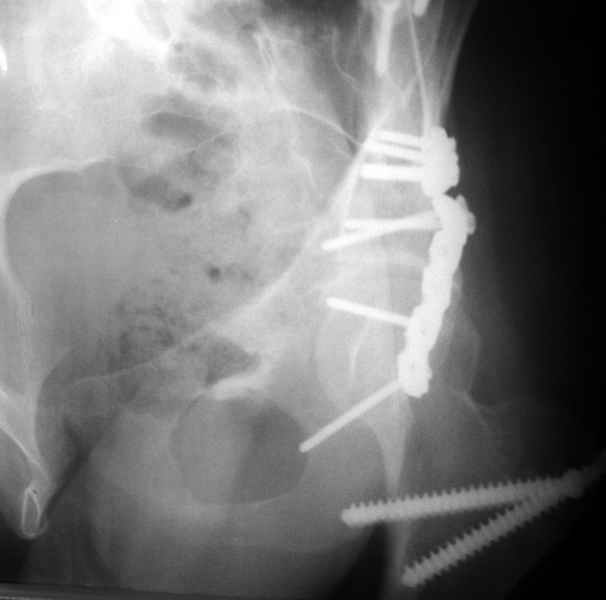

Посылаю схемы и 3D реконструкцию подобного повреждения. Называется он полным высоким двухколонным переломом вертлужной впадины, а "переломы крыла и тела подвздошной кости" входят в это понятие.

прикладываю схему доступа и случай.